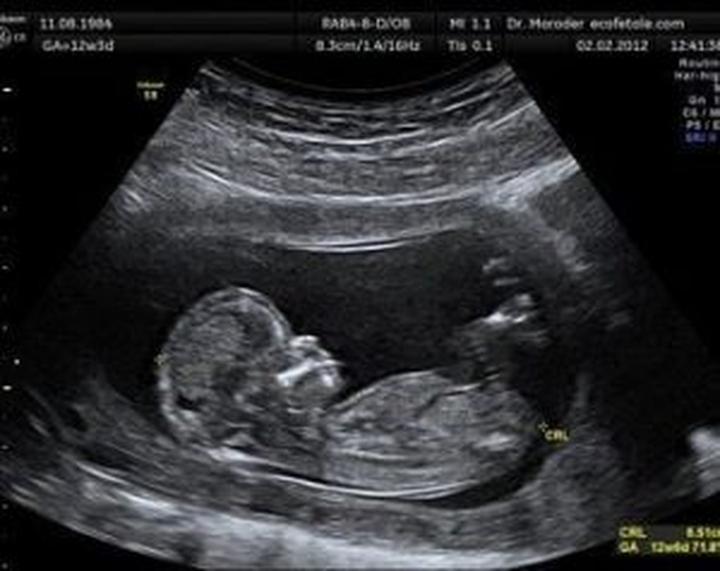

Ultrasonografia, szeroko znana jako USG, stanowi nieodłączny element życia ciężarnych kobiet, które nie wyobrażają sobie bez niej codzienności. Ta metoda diagnostyczna nie tylko skutecznie wykrywa ewentualne zagrożenia, ale również buduje silną emocjonalną więź pomiędzy rodzicami a ich pociechą. Czy jednak można mieć jakiekolwiek obawy? Badania naukowe wyraźnie pokazują, że nie ma się czego bać! Przez cztery dekady stosowania USG u kobiet w ciąży nie odnotowano praktycznie żadnych negatywnych skutków dla rozwijających się płodów. Tak samo jak Piotruś (później, w brzuszku mamy, trochę się porusza), tak aparaty USG radzą sobie z obrazowaniem, a ich moc pozostaje ograniczona do absolutnego minimum.

Chcąc uspokoić serca matek, które zadają sobie pytanie: „A co, jeśli to jednak szkodzi?”, warto przytoczyć zalecenia Światowej Organizacji Ultrasonografii w Medycynie i Biologii. Eksperci podkreślają, że ryzyko szkodliwego wpływu rutynowego badania w pierwszym trymestrze ciąży jest minimalne. Naukowcy przeanalizowali dwa główne mechanizmy działania – termiczny i kawitacyjny. Jeśli jednak podczas badania zastosujemy technologię dopplerowską, zaleca się zachowanie ostrożności w pierwszym trymestrze, ponieważ może ona podnieść temperaturę ciała o 1,5°C. W takich momentach lepiej skupić się na podglądaniu malucha na monitorze, zamiast nasłuchiwać jego dźwięków!

Badanie USG ma na celu wczesne wykrycie wszelkich nieprawidłowości rozwojowych, co da lekarzowi szansę na szybkie podjęcie ewentualnych działań. Każde z trzech głównych badań USG zaplanowane jest z myślą o danym etapie ciąży: od potwierdzenia bicia serca w pierwszym trymestrze, przez szczegółowe sprawdzenie anatomii w drugim, aż po ocenę wzrostu i położenia płodu tuż przed porodem. To trochę jak układanie puzzli, gdzie każdy kawałek jest równie ważny, a USG pomaga w ich połączeniu, zwłaszcza gdy chodzi o zdrowie maluszka!

• Potwierdzenie bicia serca w pierwszym trymestrze

• Sprawdzenie anatomii płodu w drugim trymestrze

• Ocena wzrostu i położenia płodu przed porodem